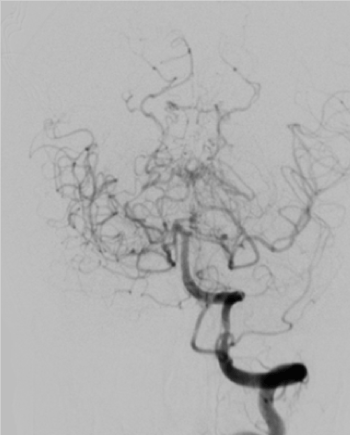

CT brain which reveals bilateral diffuse subarachnoid hemorrhage and dilated ventricles (Figure 1). CT cerebral angiography reveals no aneurysms associated with diffuse narrowing of supraclinoid portions of both internal carotid arteries (Figure 2). Diagnostic angiography of right internal carotid artery reveals diffuse narrowing of the supra-clinoid portion (Figure 3). Diagnostic angiography of left internal carotid artery reveals diffuse narrowing of the supra-clinoid portion with multiple collaterals (Figure 4). Diagnostic angiography reveals multiple meningeal collaterals (Figure 5).

Figure 4. AP view of diagnostic angiography of left internal carotid artery reveals diffuse narrowing of the supra-clinoid portion with multiple collaterals